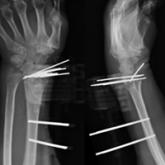

Treating Unstable Distal Radius Fractures With a Nonspanning External Fixation Device: Comparison With Volar Locking Plates in Historical Control Group

We conducted a study to compare functional and radiographic outcomes of unstable comminuted intra-articular distal radius fractures treated with a...